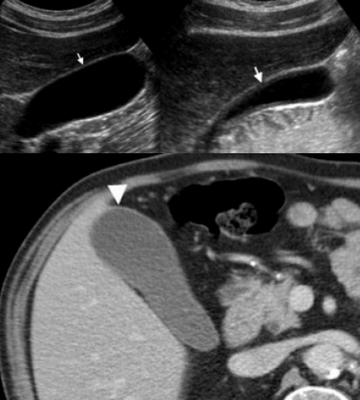

(Слева) На аксиальной КТ с контрастным усилением определяется частичное обызвествление стенки желчного пузыря. Обратите внимание на плохо различимое образование мягкотканной плотности в просвете желчного пузыря и нечеткую границу с прилежащими отделами печени.

(Справа) На аксиальной КТ с контрастным усилением визуализируется дискретное объемное образование в желчном пузыре («классическая» картина рака желчного пузыря). Для рака желчного пузыря более типичным является ограниченное, а не диффузное обызвествление стенки.

3. КТ признаки фарфорового желчного пузыря:

• Кальцинаты в стенке желчного пузыря могут иметь различную толщину (могут быть «тонкими» или «толстыми» и неправильными):

о Стенка может быть обызвествлена целиком или частично

• КТ наиболее чувствительный метод, позволяющий идентифицировать кальцинаты